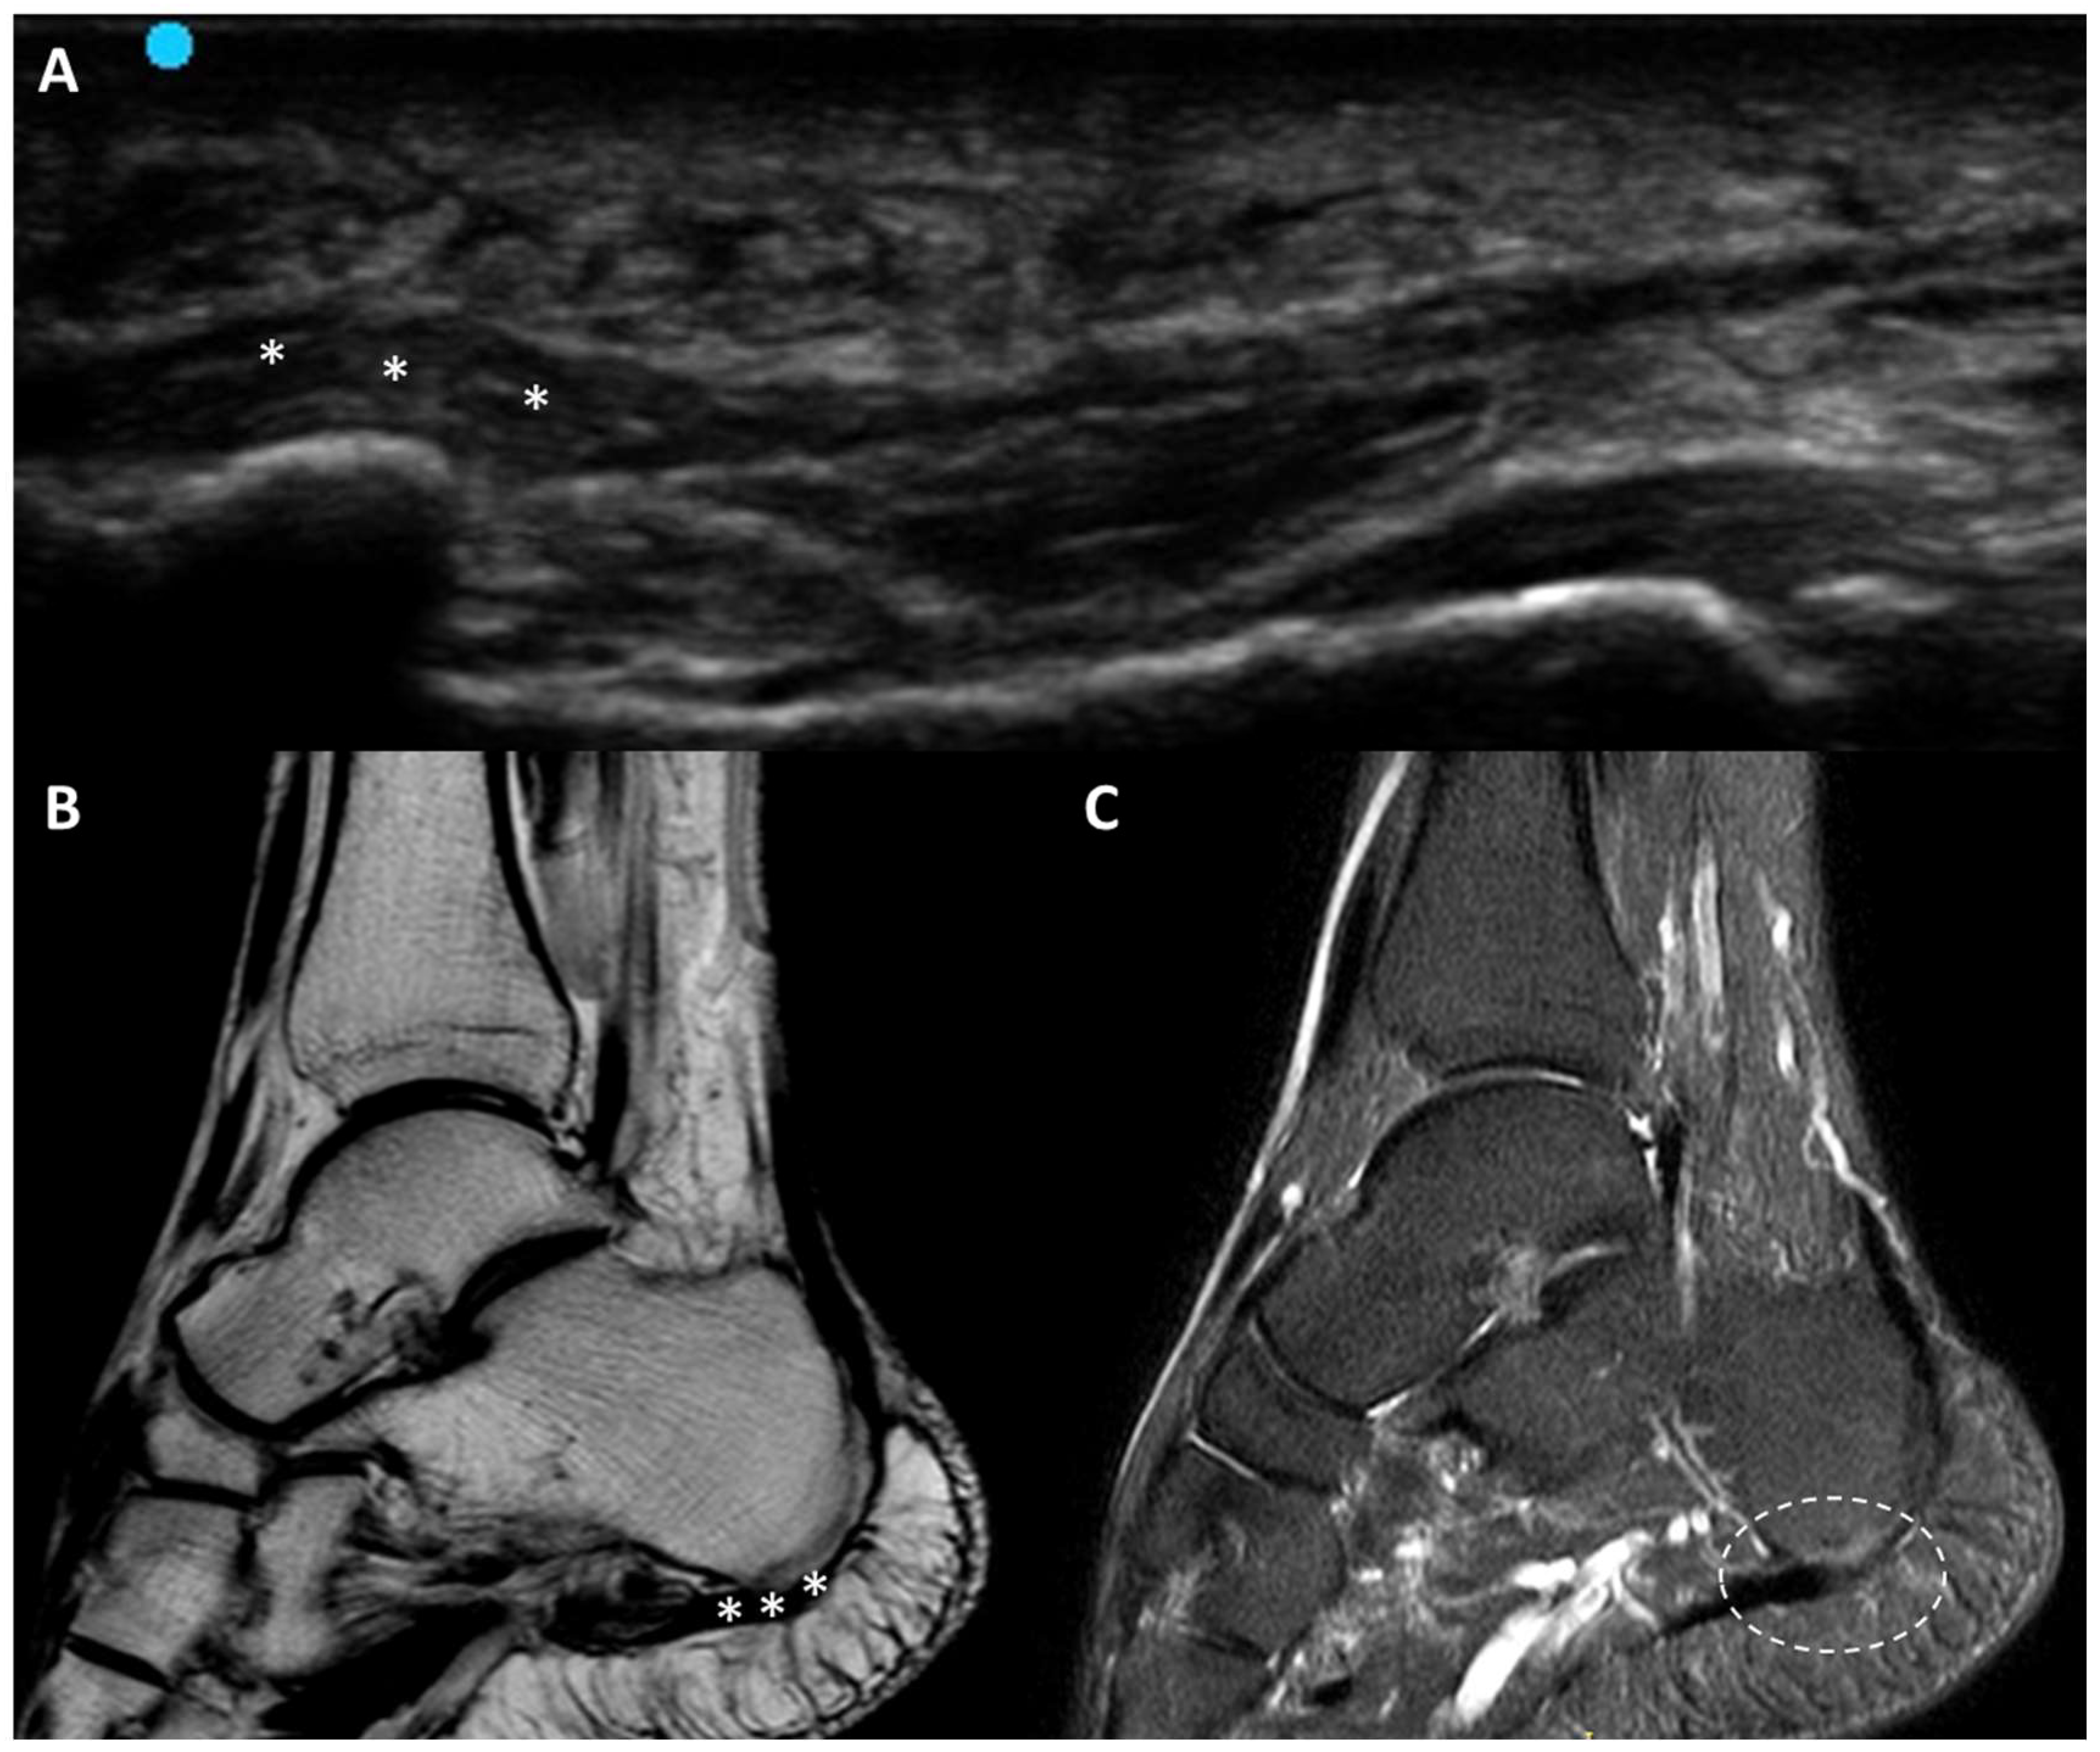

3.5.6. Plantar Fascial Rupture